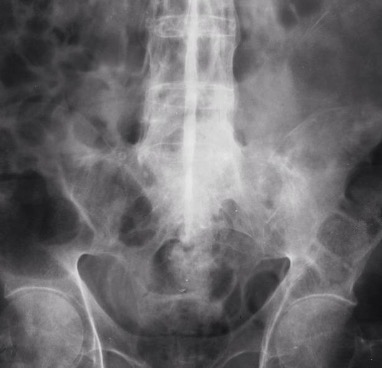

Ankylosing Spondylitis ⭐

First manifests in Sacroiliac joints:

Widening or fusion of SIJ’s